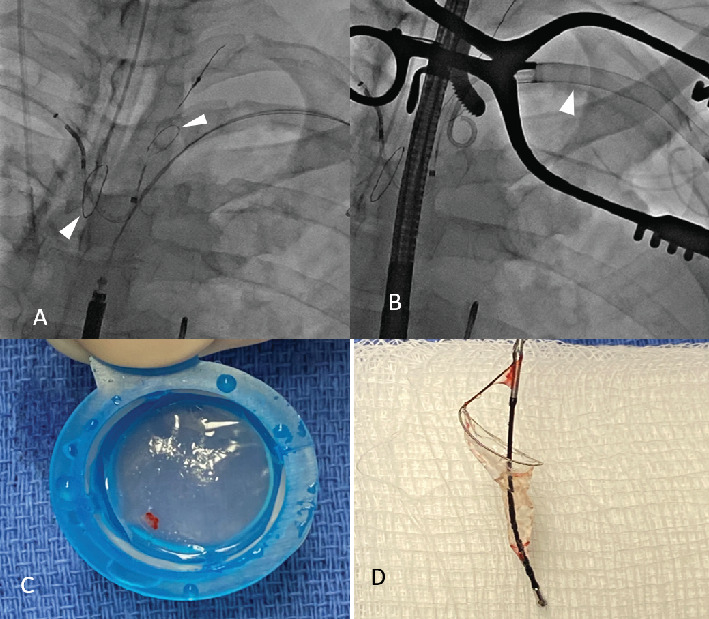

Mechanical circulatory support devices, such as the Impella catheter (Abiomed, Danvers, Massachusetts), continue to become more commonplace in patients undergoing high-risk percutaneous coronary intervention (PCI) or those in cardiogenic shock. Thrombus in the left ventricle is a contraindication to Impella placement. Here, we present a patient with an anterior ST elevation myocardial infarction who underwent primary PCI with subsequent development of cardiogenic shock followed by Impella placement, who then later developed an LV thrombus. The Impella was removed after placement of a Sentinel cerebral protection device (Boston Scientific, Massachusetts). The left carotid filter of the Sentinel captured a thrombus fragment. The patient did not have any neurological compromise. This case represents the first report of actual capture of LV thrombus by a Sentinel system in this context. The case suggests the potential value of the Sentinel cerebral protection device to lower the risk of an embolic event during Impella removal in selective clinical scenarios.